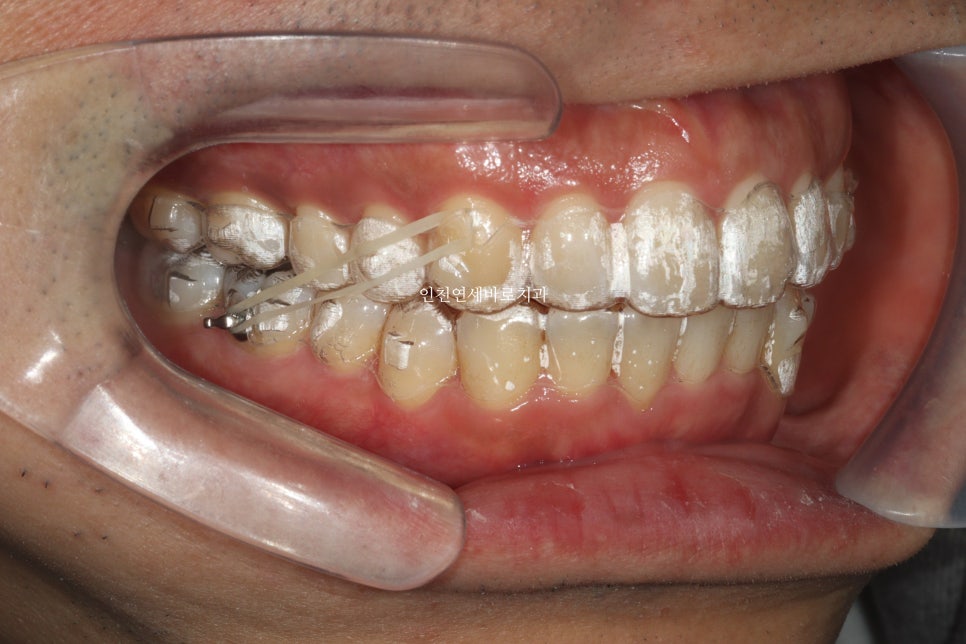

약 1달의 제작기간이 소요된 후 2023.5.17에 치료를 시작하셨습니다.

한번의 재제작을 시행하였습니다.

치료 전과 후의 비교입니다.

1회의 재제작.

각 제작마다 1달의 시간 소요

실질 치료기간 약 1년입니다.